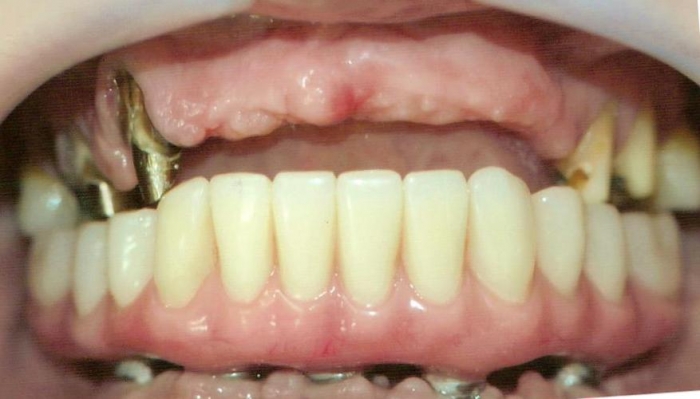

Implantes inferiores e prótese provisória inferior em Junho de 2014 - Clínica Cliniface

Implantes inferiores e prótese provisória inferior em Junho de 2014